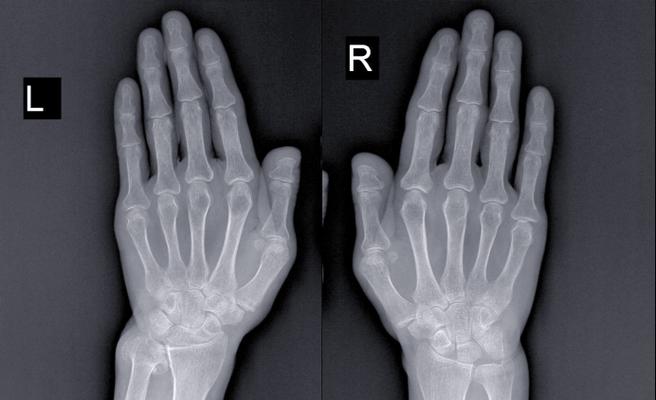

X线平片

X线是RA最基础、最常用的影像学检查方法,主要评估骨与软骨的破坏情况,RA的X线改变是一个动态发展的过程,国际通用的评估标准是Sharp/van der Heijde评分系统,它从侵蚀和关节间隙狭窄两个方面量化关节损害。

骨侵蚀:

(图片来源网络,侵删)- 定义:关节边缘和邻近骨皮质出现的虫噬状、穿凿样骨质缺损。

- 好发部位:

- 手、足小关节:最典型的部位是近端指间关节、掌指关节、跖趾关节。

- 腕关节:尤其是尺骨茎突、桡骨远端、月骨、三角骨等部位。

- 股骨髁、胫骨平台等大关节。

- 特点:侵蚀灶通常位于关节边缘,与关节软骨相邻,这是滑膜血管翳从关节边缘向骨内侵袭的直接证据,典型的侵蚀形态是“穿凿样”,边缘清晰,可有硬化边。